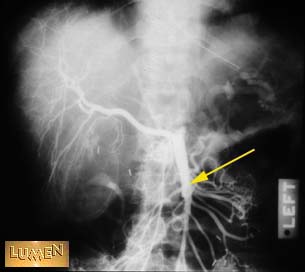

Question: Identify.

Answer

Superior mesenteric a.